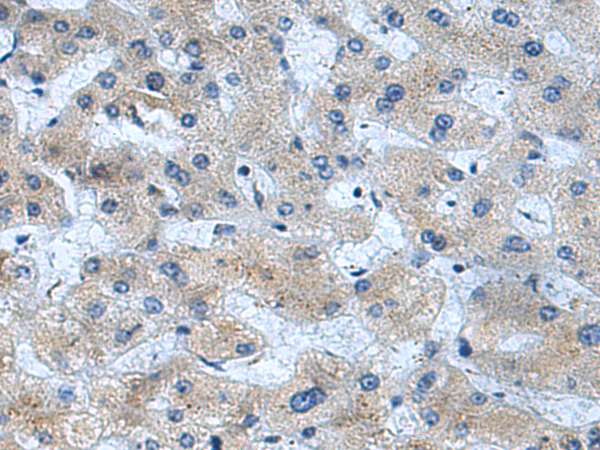

分类: 科研抗体货号: P08937别名:应用: IHC反应种属: Human